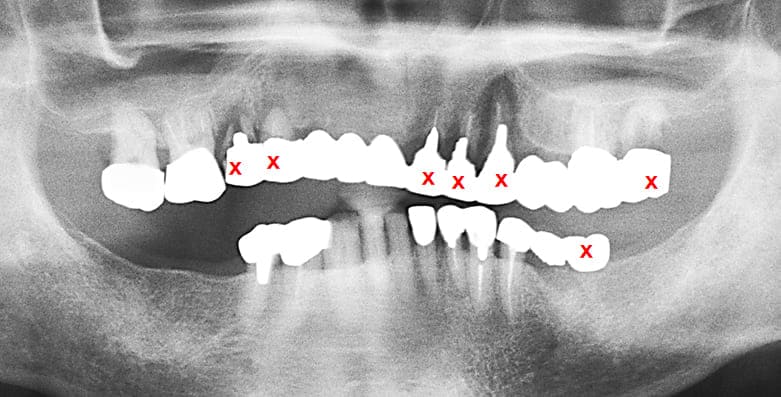

初診時のパノラマXP所見

上顎前歯を含む第2小臼歯から対側の第2小臼歯までの10本のブリッジが脱離しそれを支えていた歯自体が保存できない状態であった。また下顎の臼歯部も欠損しており、このことで垂直的な咬合の安定が得られず前歯に負担がかかる崩壊脱離したと考えられる。

#15,14,21,22,23,27,36が残根状態で温存は不可能であり、患者さん自身もそれを自覚しておられた。

治療計画

- 保存できない上顎の前歯(残根)を抜歯

- 両側上顎臼歯部にインプラントを埋入して上顎臼歯部は、温存してvertical stopを作り前歯部も含めて咬合を安定させる